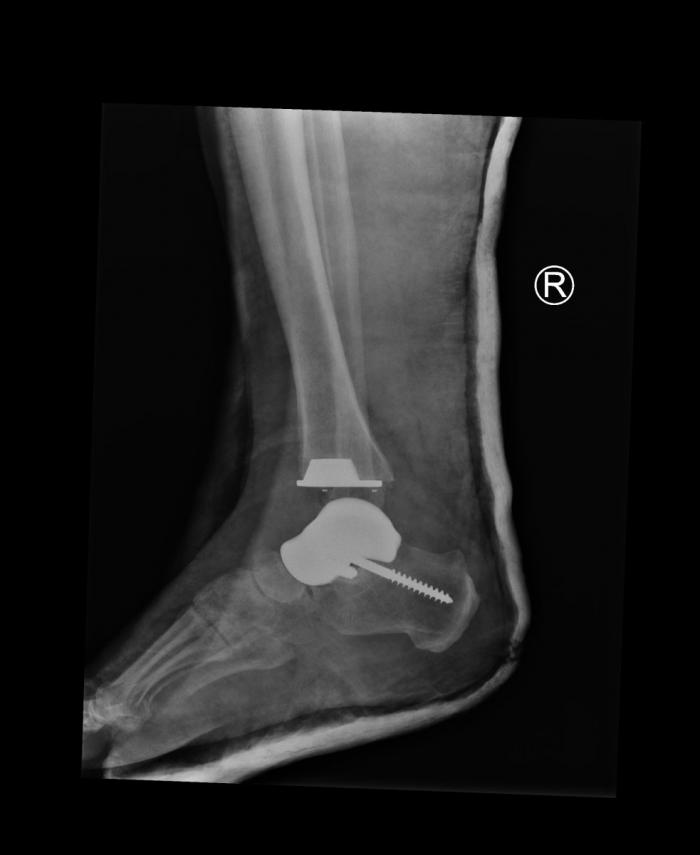

W szpitalu klinicznym nasi lekarze, w dniu 14 grudnia 2023 r., wykonali skomplikowany zabieg wszczepienia implantu kości skokowej custom made.

Warto podkreślić, że tego rodzaju innowacyjny i skomplikowany zabieg nasi specjaliści wykonali wcześniej w buskim szpitalu. Był to jeden z pierwszych zabiegów w Polsce z wykorzystaniem implantu kości skokowej custom made czyli „szyte na miarę” i dopasowywane indywidualnie do pacjenta. Pacjent miał już za sobą pierwotny i rewizyjny zabieg endoprotezoplastyki stawu skokowego. Kolejna operacja stanowiła wyzwanie, ponieważ w jego przypadku nie można było już zastosować konwencjonalnej protezy z powodu dużych ubytków kostnych. Spersonalizowana endoproteza powstała na podstawie badania tomografii komputerowej. Stworzono implant, który był idealnie dopasowany do budowy kości pacjenta. Odwzorowano powierzchnie stawowe pacjenta oraz fizjologiczny ruch stawu z maksymalnie osiągalną dokładnością – 0,1 mm.